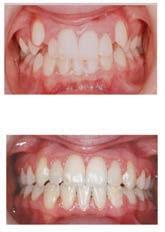

๊ฑด๊ฐํ ๋ฏธ์, ํดํผ์ค๋ง์ผ ์น๊ณผ์์

์์ํ์ธ์.

์ต์ ์ฅ๋น์ ์น์ ํ ์ง๋ฃ, ์ํ๋ํธ๊น์ง ๋ฏฟ๊ณ ๋งก๊ธฐ์ธ์!

๊ฐ์กฑ ๋ชจ๋์ ๋ฐ์ ๋ฏธ์๋ฅผ ์ง์ผ์ฃผ๋ ํดํผ

์ค๋ง์ผ ์น๊ณผ์์๋ ๊ฑด๊ฐ๋ณดํ๊ณผ ๋ฉ๋์ผ์ด,

๋ค์ํ PPO ๋ณดํ์ ์ทจ๊ธํ๋ฉฐ, ์์ฝ๋ถํฐ

์ง๋ฃ๊น์ง ๋ชจ๋ ๊ณผ์ ์์ ํ์์ ํธ์์

๋ง์กฑ์ ์ต์ฐ์ ์ผ๋ก ํ๋ค.

ํนํ ํดํผ์ค๋ง์ผ ์น๊ณผ๋ ์ํ๋ํธ ์น๋ฃ

์ ๊ฐํ ์์ ๊ฐ์ ๊ฐ์ง๊ณ ์๋๋ฐ, ์์์

์น์ ๋ ์ฌ์ฉํ๋ ํ, ์ฆ ์น์์ ํฑ ๊ทผ์ก

์ ์ฌ์ฉํ์ฌ ์์์ ์๊ฒ ๋ถ์๋ ๋ฅ๋ ฅ๊ณผ

์ฌ๋ฏธ์ฑ์ ๋์์ ๋ง์กฑ์ํค๋ ์ํ๋ํธ๋

์์ฐ ์น์์ ๊ฐ์ฅ ๊ฐ๊น์ด ๋์ฒด ์น๋ฃ๋ก, ํ

๋์ ๋นํด ๋ ๋จ๋จํ๊ณ ์ค๋ ์ฌ์ฉํ ์ ์

์ธ์ ์น์๋ฅผ ๊น์ ํ์๊ฐ ์์ด ๊ตฌ๊ฐ ๊ฑด๊ฐ์ ์ ์งํ๋ ๋ฐ๋ ๋์์ด ๋๋ค. ํดํผ์ค๋ง์ผ ์น๊ณผ๋ ๋ณต์กํ ๊ตฌ๊ฐ์ธ๊ณผ ์์ ๊ณผ ์ง๋จ์ ์ํด ์น๊ณผ์ ์ฉ 3D CT ์ค์บ๋๋ฅผ ๊ฐ์ถ๊ณ ์์ผ๋ฉฐ, ์ด๋ฅผ ํตํด ์ ํํ๊ณ ์์ ํ ์ํ๋

ํธ ์์ ์ด ๊ฐ๋ฅํ๋ค. ํฑ๋ผ ์ํ, ์ ๊ฒฝ ์์น, ๋ผ์ ๋ฐ๋๊น์ง ์ ๋ฐํ๊ฒ ๋ถ

์ํ์ฌ ํ์ ๊ฐ๊ฐ์ธ์๊ฒ ์ต์ ํ๋ ์น๋ฃ ๊ณํ์ ์๋ฆฝํด๋๋ฆฐ๋ค.

๋ฟ๋ง ์๋๋ผ, ์ฌ๋ฏธ๋ณด์ฒ ๊ณผ ๋ฏธ์ฉ์น๋ฃ, ์ผ๋ฐ์น๊ณผ, ์์์น๊ณผ, ๊ตฌ๊ฐ์ธ๊ณผ, ์ ๊ฒฝ

์น๊ณผ ๋ฑ ๋ค์ํ ๋ถ์ผ์ ์ ๋ฌธ ์๋ฃ์ง์ด ํจ๊ปํด ํ ํ ์น๊ณผ ์ง๋ฃ๋ฅผ ์์คํฑ ์ผ๋ก ์ ๊ณตํ๊ณ ์๋ค.

ํดํผ์ค๋ง์ผ ์น๊ณผ์์๋ ์ ํธ๋(Aetna), ์ค์ฌ(Anthem), ํด๋ ๋ฒ์ผ์ด (Clever Care), ์์คํฐ๋ฐ(Astiva), ํด๋จธ๋(Humana), ๋ฆฌ๋ฒํฐ(Liberty), ์ ๋ ์ดํฐ๋ํฌ์ค์ผ์ด(United Healthcare) ๋ฑ. ๋ค์ํ ๋ณดํ์ ์ทจ๊ธํ๊ณ ์๊ณ , ๋ฉ๋์นผ/๋ฉ๋์ผ์ด PPO ๋ณดํ ํ์ํ๋ค.

์ข์ ์ฌ๋ฃ์ ๊ณ ํ์ง ์ง๋ฃ, ์ต์ ๊ธฐ์ , ๊ทธ๋ฆฌ๊ณ ํ์๋ฅผ ์๊ฐํ๋ ์ง์ฌ์ด ์๋ ํดํผ์ค๋ง์ผ ์น๊ณผ์์ ์จ ๊ฐ์กฑ์ ๊ฑด๊ฐํ ๋ฏธ์๋ฅผ ๋์ฐพ์๋ณด์.

๋ฌธ์ ๋ฐ ์์ฝ: 818-775-1200